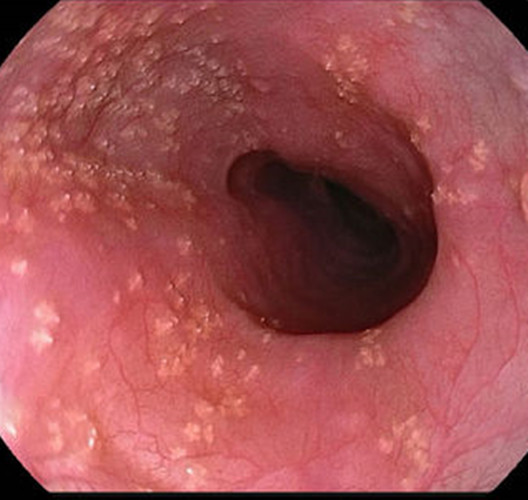

消化道白色念珠菌感染